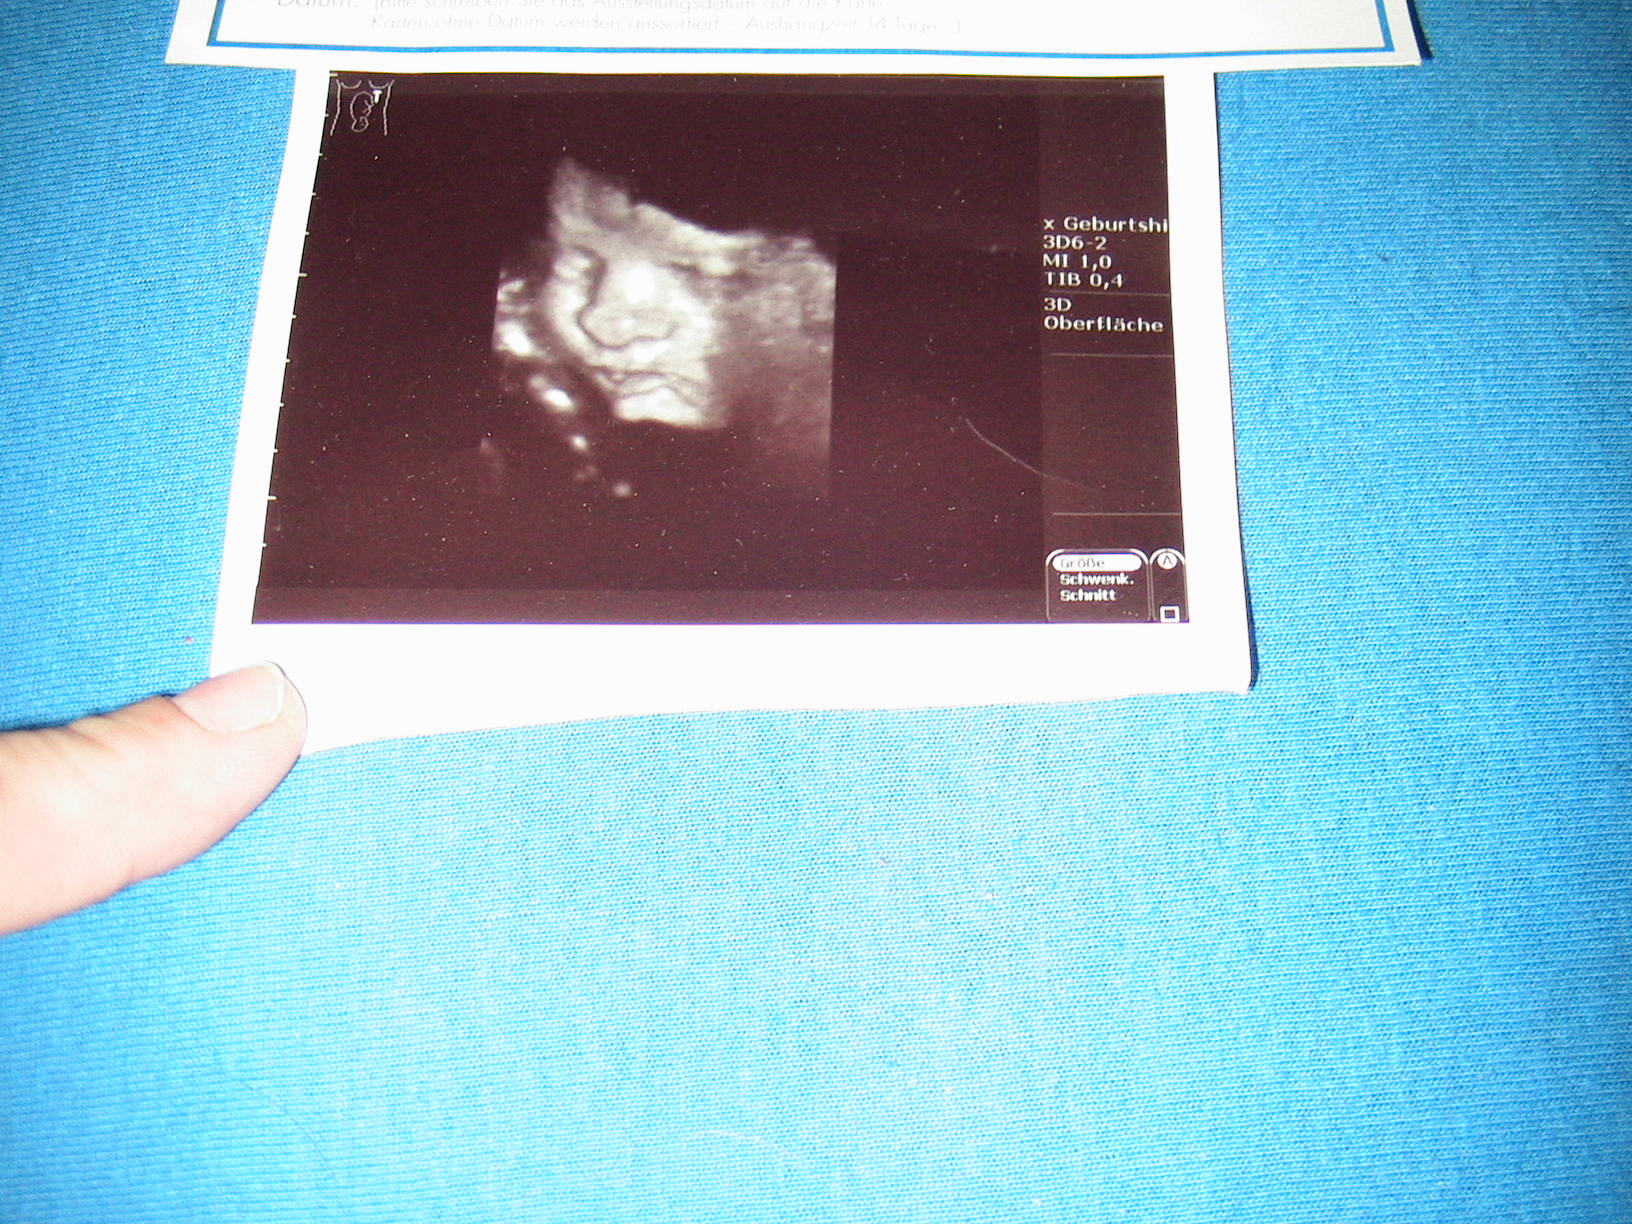

Bea,schön das du wieder da bist,im Krankenhaus musste ich liegen und bekamm Magnesium Infusionen und jeeden Tag 2mal ctg die Ärzte meinten das er schwer Aktiv ist oh oh mal gespannt wenn er auf der welt ist habe auch schöne bilder bekommen werde sie die die Tage mal einstellen.

Nadja, die Bilder sind echt der Wahnsinn man sieht alles so genau - unfassbar - gabs zu meiner Zeit noch nicht. Tja ich bin damals fast geplatzt vor lauter Spannung wie mein Mädele den aussehen wird........ und du weißt es schon. Echt ein süsser Fratz, freue mich schon auf die Original-Fotos. Hoffe du hast einen guten Foto.